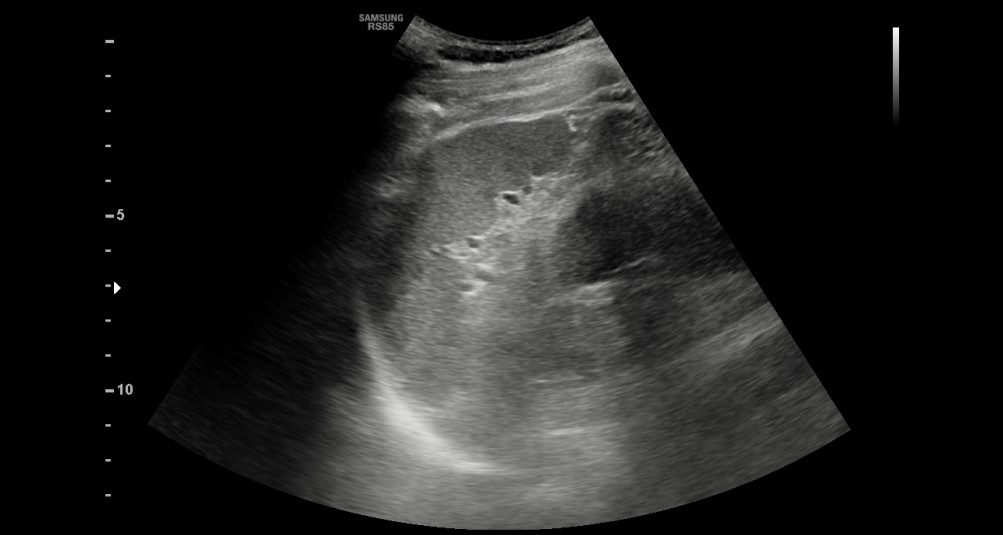

[366,Hepatobiliary [HB]] 62/M,Abnormal finding on upper abdominal ultrasonography during a health check-up

Hepatobiliary [HB]

US,

What is the most likely diagnosis?